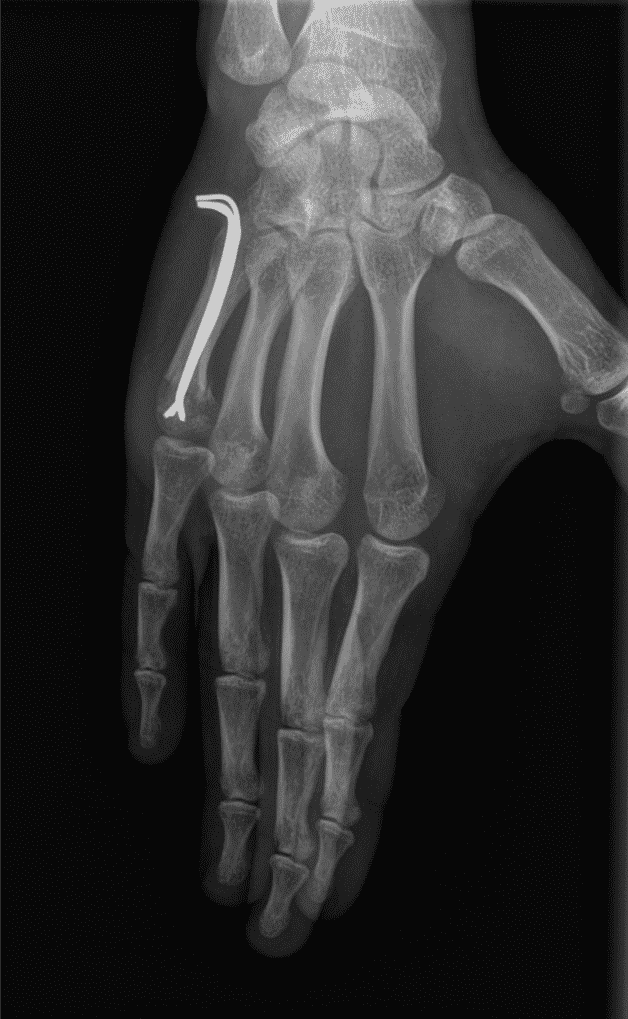

Au niveau de la métaphyse métacarpienne on préfère généralement les vissages ou les plaques. On accède à l'os par une incision sur le dos de la main. Le matériel ne se retire pas systématiquement. Si l'on décide de l'enlever, on attend en général une année.

Lorsque le trait de fracture est transversal, comme ci-dessus, la plaque est préférable. En revanche dès que la fracture présente un trait oblique et long, il est possible de ne réaliser qu'un vissage.

Assez souvent, la fixation de la diaphyse des métacarpiens nécessite une immobilisation par attelle intrinsèque plus dans les suites. Comme précédemment, la durée varie de 1 mois à 6 semaines.